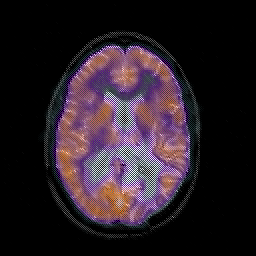

Glioblastoma multiforme overlay -- Slice #31

[Home][Help][Clinical][Tour 1][Tour 2][Tour 3] Slice 31